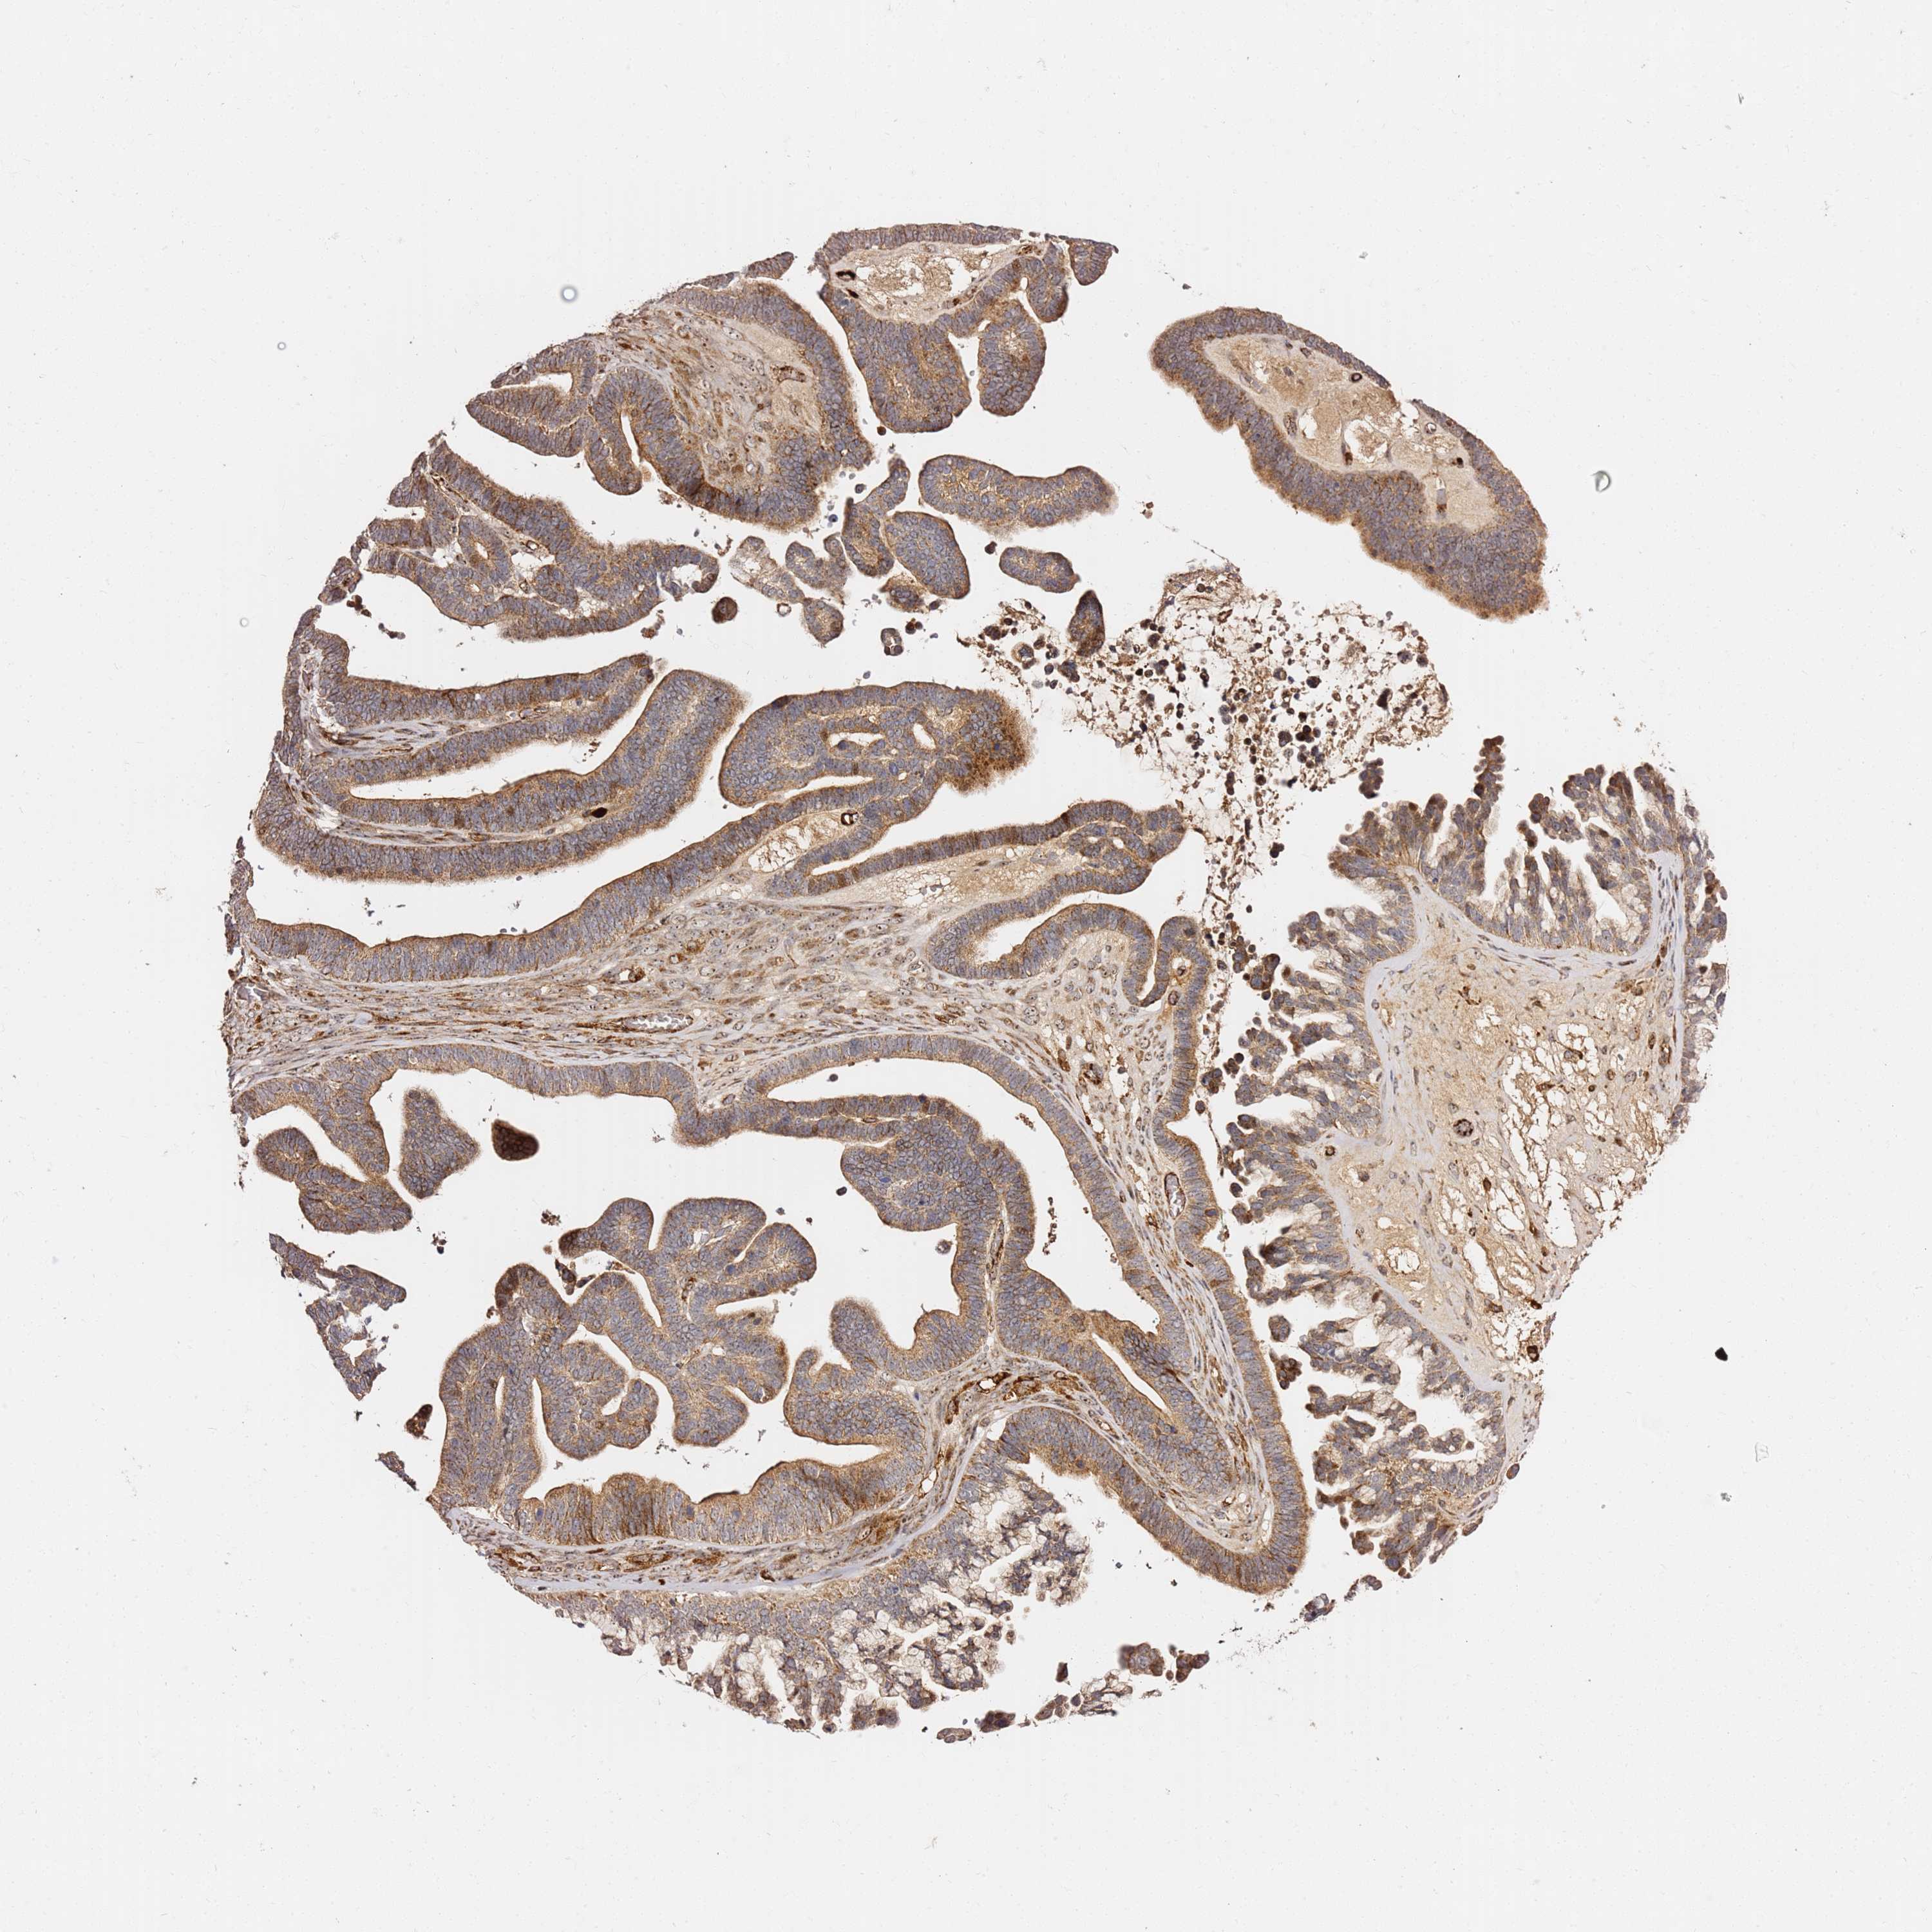

OVARIAN CANCER - Protein expressioni

A mouse-over function shows sample information and annotation data. Click on an image to view it in a full screen mode. Samples can be filtered based on level of antibody staining by selecting one or several of the following categories: high, medium, low and not detected. The assay and annotation is described here.

Note that samples used for immunohistochemistry by the Human Protein Atlas do not correspond to samples in the TCGA dataset.

Antibody stainingi

Antibody staining in the annotated cell types in the current human tissue is reported as not detected, low, medium, or high, based on conventional immunohistochemistry profiling in selected tissues. This score is based on the combination of the staining intensity and fraction of stained cells.

Each image is clickable and will lead to virtual microscopy that enables deeper exploration of all samples and also displays staining intensity scores, fraction scores and subcellular localization as well as patient and tissue information for each sample.

Antibody HPA046153

Staining

High

Medium

Low

Not detected

Intensity

Strong

Moderate

Weak

Negative

Quantity

>75%

75%-25%

<25%

None

Location

Nuclear

Cytoplasmic/membranous

Cytoplasmic/membranous,nuclear

Cystadenocarcinoma, serous, NOS

Carcinoma, endometroid

Cystadenocarcinoma, mucinous, NOS

Carcinoma, NOS